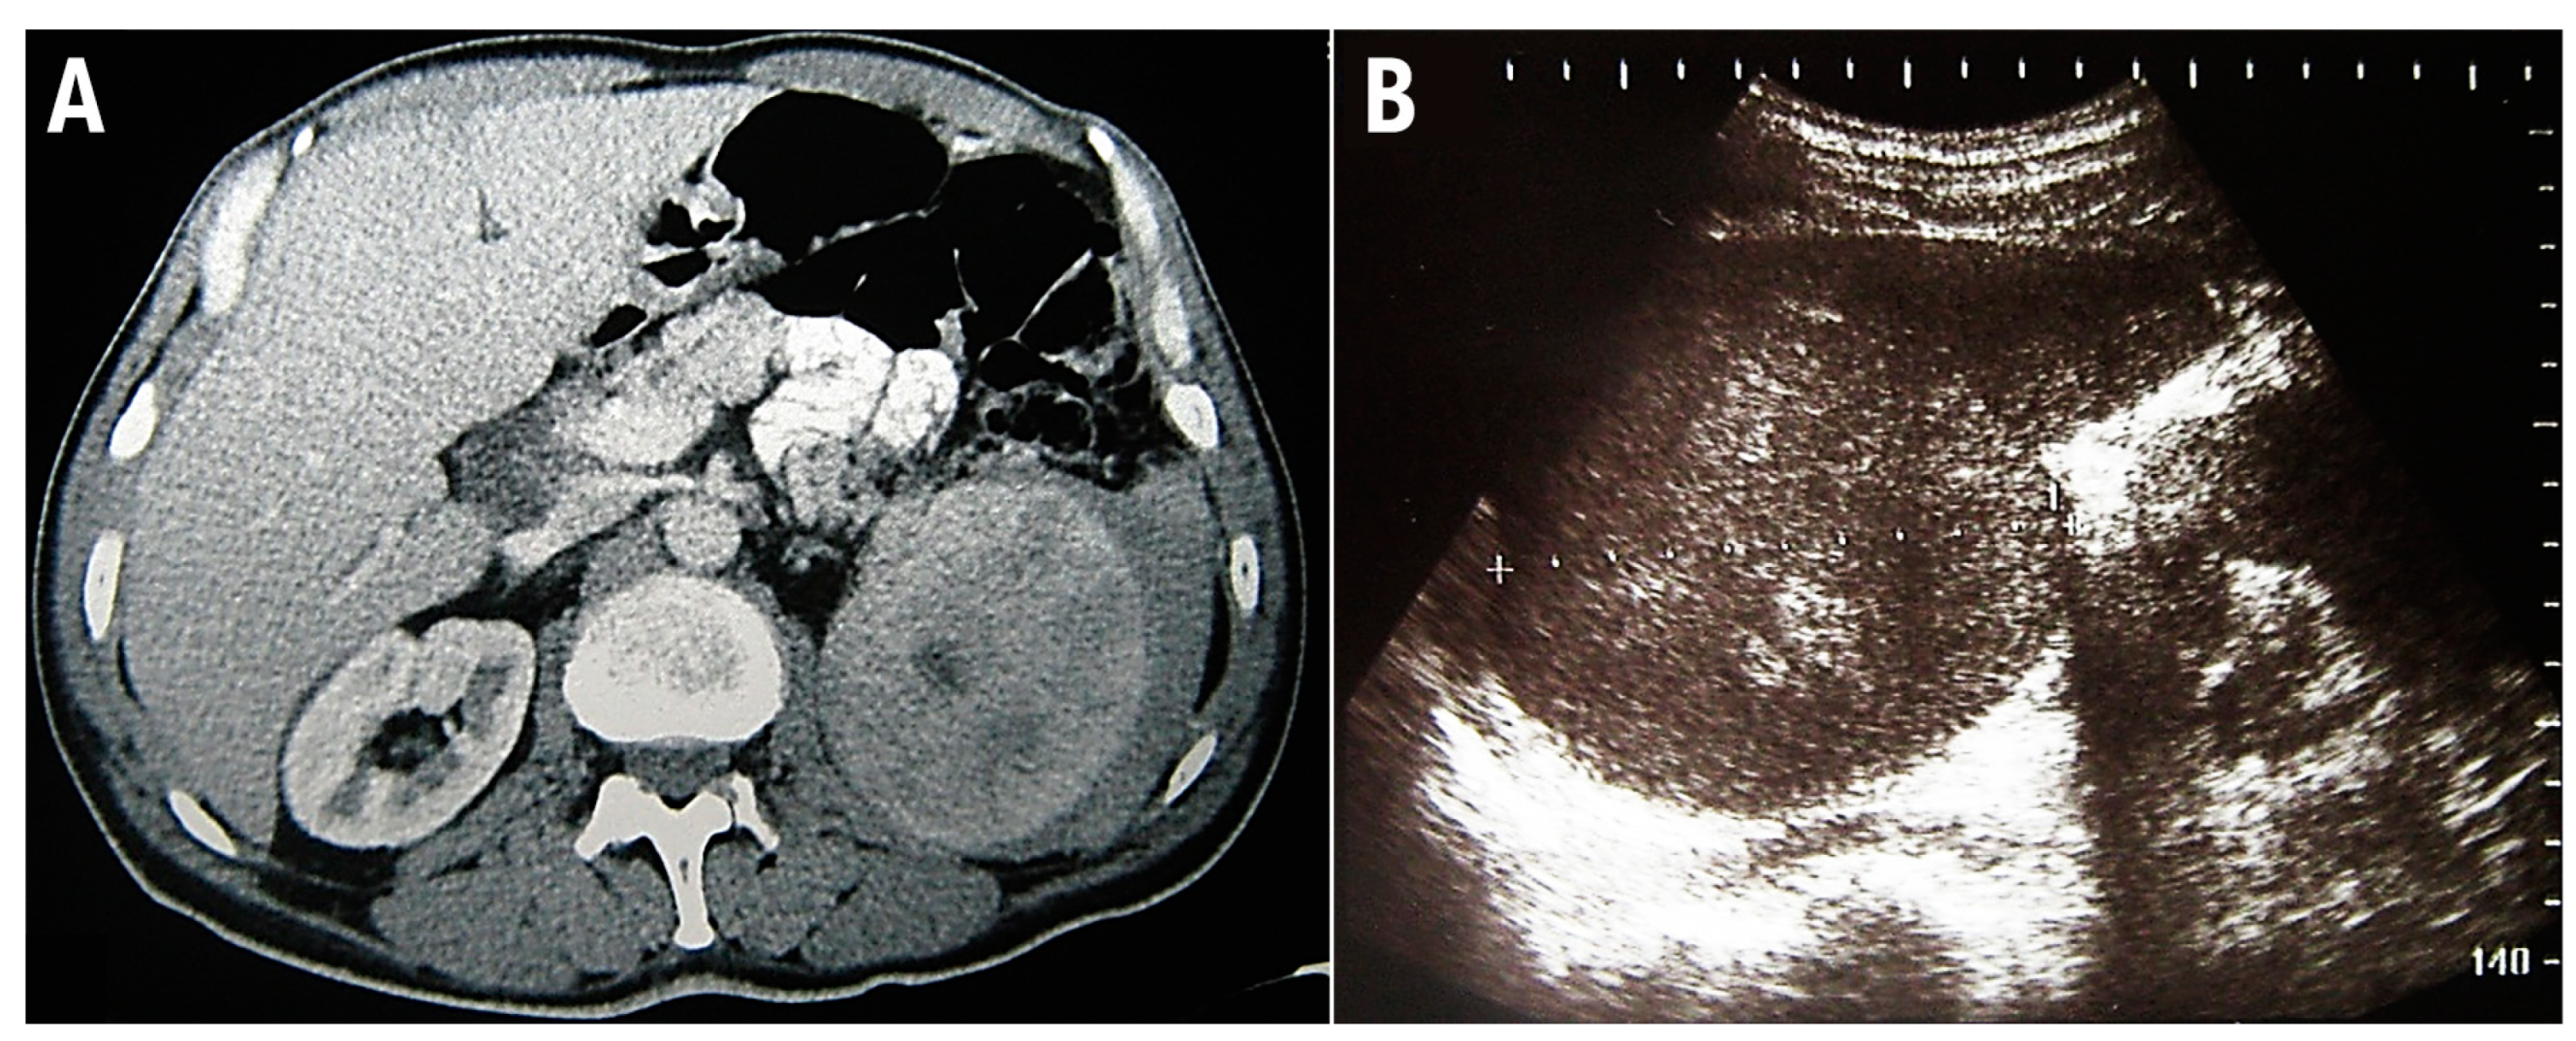

2. Case Report